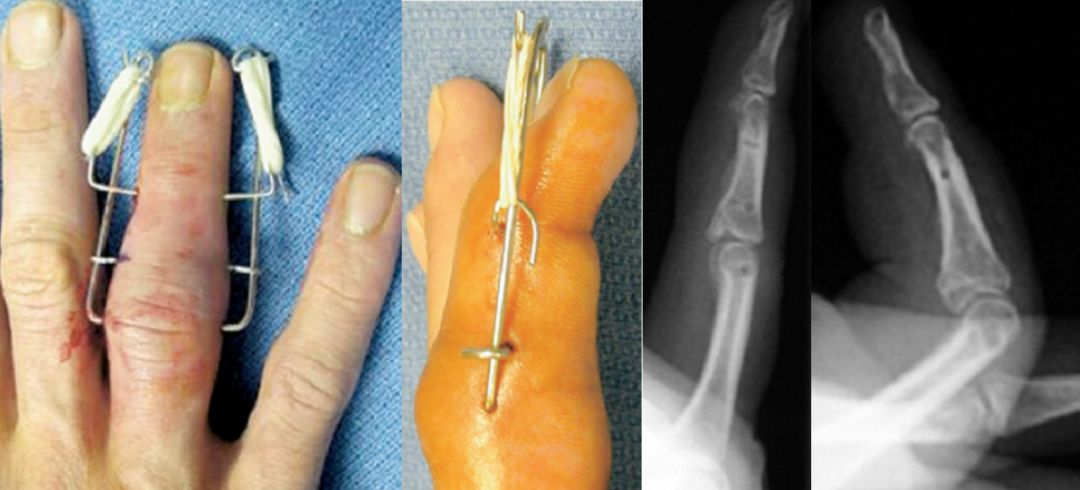

石墨法:对于伸肌腱止点撕脱骨折型的锤状指,利用克氏针的阻挡作用,可以将末节基底背侧的骨折块复位并卡压固定。

改良版石墨法:改良的石墨法,利用的是克氏针的弹性原理巧妙地将远位指间关节背伸,这样操作更利于骨折的愈合。

10、克氏针的支撑作用

遇到内踝骨折短缩通常需要抗滑或支撑固定,利用U型针可以起到支撑固定作用。

11、克氏针的悬吊固定作用

对于近节指基底粉碎压缩性骨折,利用U型克氏针的悬吊固定作用,可以比较好的维持骨折的高度。